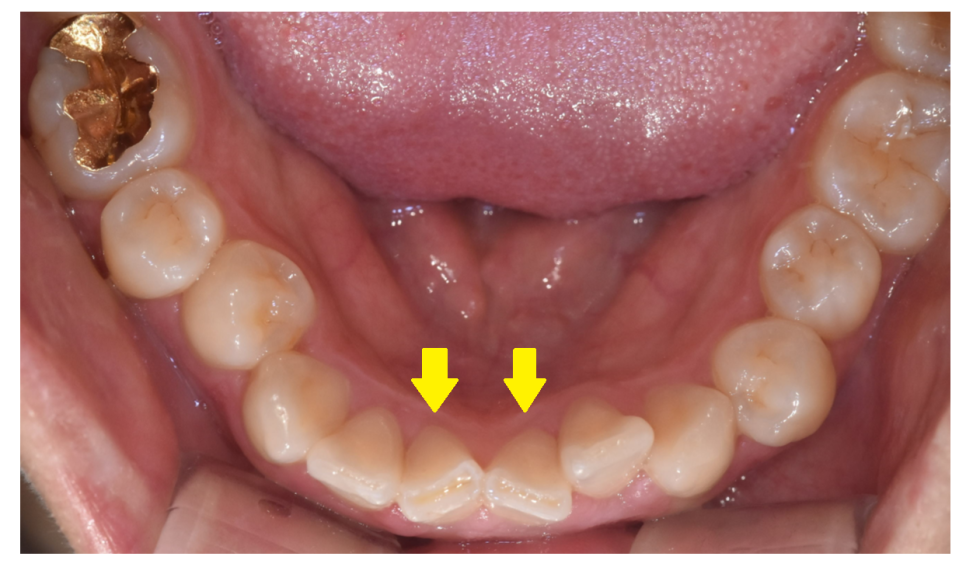

250430

아래 앞니가 윗니에 지속적으로 닿으며 마모되거나,

윗니가 아랫니를 강하게 누르면서 깨질 수 있습니다.

250430 깊게 물려 깨지고 닳은 앞니